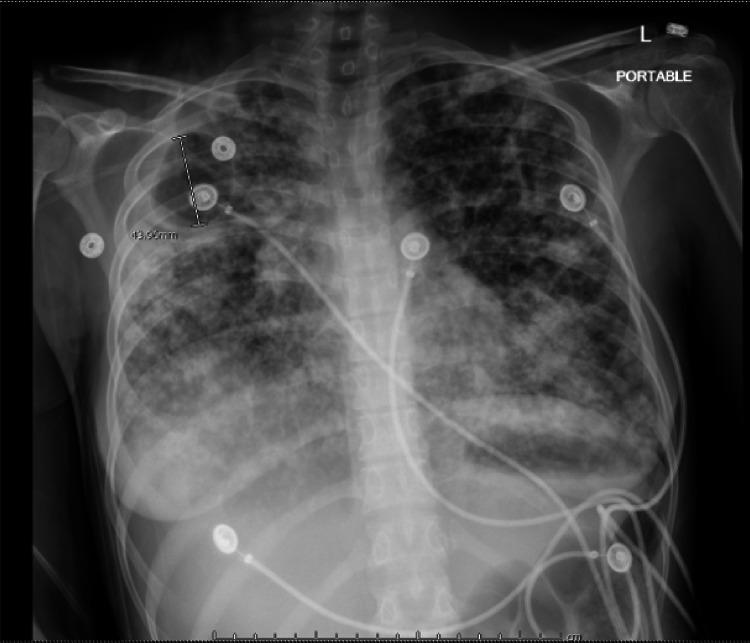

Tuberculosis (TB) disease affects a large population worldwide but is often missed. Early diagnosis can be challenging at times due to failure to include TB in the differential diagnoses. Tuberculosis is a treatable disease but it can lead to undesirable consequences if left untreated. Here we report a case of a young Guatemalan woman presented with respiratory failure and extensive lung opacification on imaging who went into cardiac arrest. Post resuscitation, workup was significant for (TB) on sputum smear. Despite appropriate treatment, she expired. The aim of this paper is to summarize TB complications that directly contribute to mortality as many clinicians do not consider TB as an immediate cause of death.

结核病在全球影响着大量人口,但常常被漏诊。由于在鉴别诊断中未将结核病纳入考虑,早期诊断有时具有挑战性。结核病是一种可治疗的疾病,但如果不治疗,可能会导致不良后果。在此,我们报告一例年轻的危地马拉女性病例,该患者出现呼吸衰竭,影像学检查显示肺部广泛浑浊,随后发生心脏骤停。复苏后,痰涂片检查发现(结核病)呈阳性。尽管进行了适当治疗,她仍不幸去世。本文的目的是总结直接导致死亡的结核病并发症,因为许多临床医生并不认为结核病是直接死因。